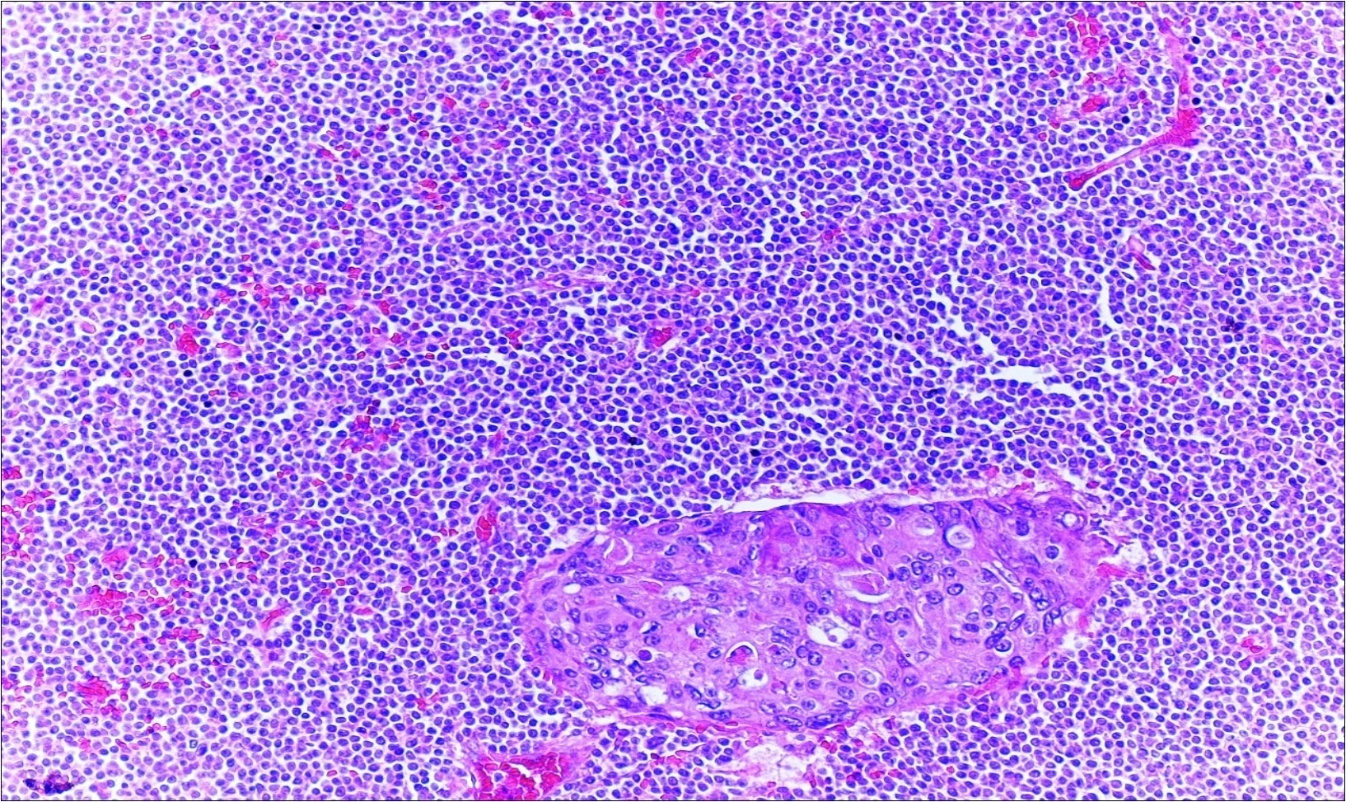

A 63-year-old woman presented to the Department of General Surgery as an outpatient with abdominal pain. Physical examination showed the signs of acute appendicitis and appendectomy was performed. During microscopic examination, a small focus of atypical monotonous lymphoid cell population was seen and the material was sampled totally. The pathological examination revealed MALT lymphoma (Figure 1), with diffuse positivity of cluster of differentiation (CD) 20 (Figure 2), CD 79a and B-cell lymphoma (Bcl- 2) (Figure 3) with just a few CD3 positive lymphoid cells. However, no evidence of adenocarcinoma was found in the appendectomy specimen. After the diagnosis of lymphoma, a complete colonoscopy was planned and this revealed a solid tumoral mass in the caecum measuring 5x4x4 cm. Computed tomography of the abdomen and pelvis revealed mesenteric lymphadenopathy associated with a mass in the caecum with multiple nodules in liver consistent with metastasis (Figure 4). Frozen sections were not obtained since the treatment method would not be affected. The patient underwent anterior resection with regional lymphadenectomy, with the pathological assessment of the resected specimen revealing a collision tumor consisting of a poorly differentiated adenocarcinoma extending through the muscularis propria with MALT lymphoma (Figure 5). Microscopic evaluation of the 11 regional lymph nodes in the mesentery of the resected colon and liver biopsy showed diffuse infiltration of MALT lymphoma with metastasis of adenocarcinoma (Figure 6). According to immunohistochemistry, atypical lymphocytes were positive for CD 20, Bcl-2, and negative for CD3, CD5, CD10, CD23, Bcl-6, terminal deoxynucleotidyl transferase, and cyclin D1. The proliferation fraction (MIB-1 immunostaining) was approximately 20%. The morphological and immunohistochemical findings were used to confirm the diagnosis of synchronous presentation of MALT lymphoma and colon adenocarcinoma within the caecum, mesenteric lymph nodes and liver metastases.

Figure 1.Appendix lumen infiltrated with B lymphoid cells (h&e;x100)

Figure 6.Adenocarcinoma with MALT lymphoma infiltration of lymph node (h&e;200)